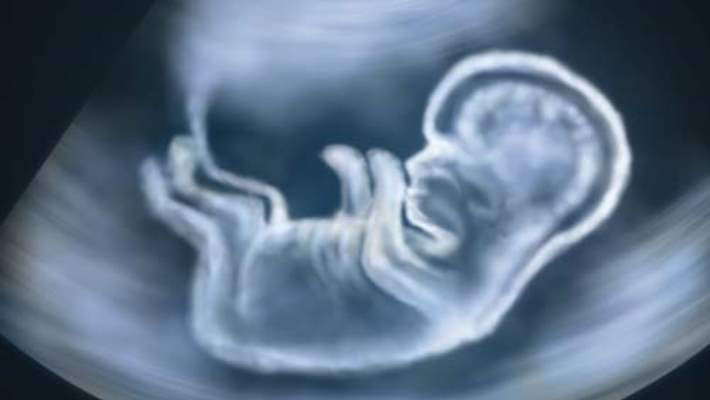

Gebeliğin 31. haftasında bebeğin hareketleri özellikle önem kazanır. Anne adayının bebeğin gün içindeki hareketlerinin özelliklerini izlemesinde yarar vardır. Hangi zamanlarda hareket ettiği, annenin hangi aktivitelerinden önce ya da sonra oynadığı izlenebilir. Normalde bebek hareketlerini saymaya gerek yoktur. Ancak yüksek riskli gebelik halinde anne adaylarının örneğin bebeğin bir saat içindeki hareketlerini saymaları önerilebilmektedir. Gebeliklerin yüzde 97’si düşük riskli olduğu için bebek hareketlerine özellikle dikkat etmeye gerek yoktur. Bir tek şeye dikkat edilmesinde yarar vardır, o da bebeğin huyunun değişmesidir. Örneğin belli zamanlarda hareket ediyorsa, artık etmeyebilir. Ya da hıçkırmıyorsa hıçkırmaya başlamış olabilir. Bunların bir riski ve fazla önemi yoktur. Bu haftalardan itibaren bebeklerin beyni daha gelişkin, hareketleri daha bilinçli ve amaçlı olacaktır. Öğrenme süreçleri başlamıştır. Örneğin bebek annenin uzun süre aynı pozisyonda kalmasından rahatsız olduğunda, bu rahatsızlığı tekme ya da yumrukla bildirecektir. Yani artık bebeğin huyunun bu haftadan itibaren değişmekte olduğu göz önünde bulundurulmalıdır.